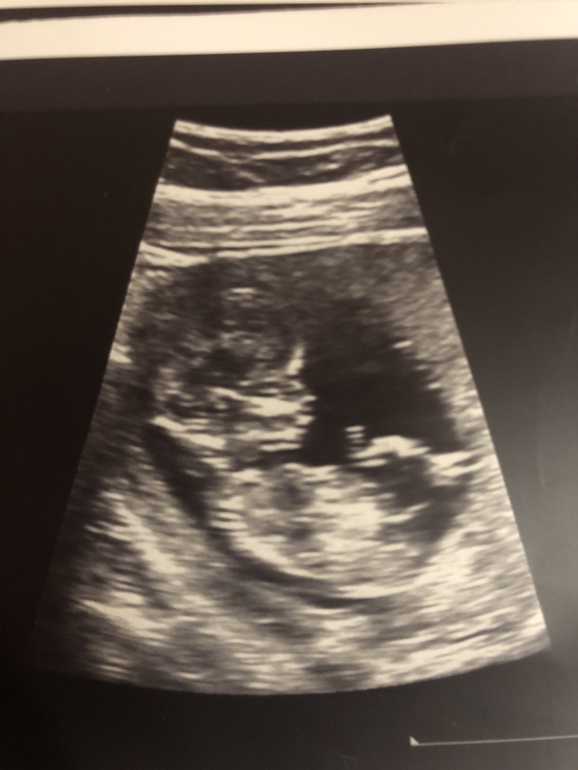

Мальчишка/ девчонка ?)

ТонусСегодня была на узи внепланово, так как потягивал пару дней живот, насмотрели небольшой тонус..

Последний раз была на узи в 6 недель, только точку увидела, а тут целый человек!)

11 недель и 6 дней срок

Не могу понять : на второй фото это половой бугорок или пуповина? Потому что на первой ничего не торчит ))

на втором фото точно не бугорок. мы только с первого скрининга сегодня, бугорок совсем не там. он возле выше копчика, ближе к ножкам.

На фото нельзя разобрать бугорок.. Да и не всегда работает этот метод, у меня был точно вверх бугорок, и даже в 16 недель сказали мальчик, а на 18 недели в жк сказали что жду девочку) Так что я за как можно более позднее определение пола.

Вряд-ли бугорок так высоко. Но лично я по ощущениям и чисто визуально за девчушку. Уж больно аккуратный ляль) мальчишки как правило как бы "угловые" что-ли, не могу слово подобрать

Но я не могу понять где этот бугорок, не вижу его) на второй фото вроде как пуповина, потому что кажется бугорок ниже должен быть ...)